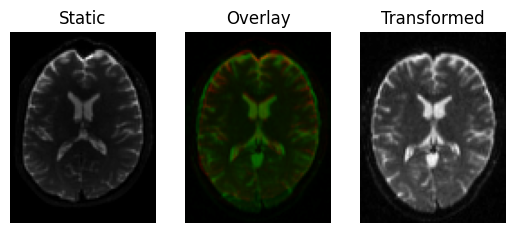

Alternatively, you can also use the register_dwi_to_template function that needs to also know about the gradient table of the DWI data, provided as a tuple of (bvals_file, bvecs_file). In this case, we are going to move the diffusion data to the B0 image (the opposite of the previous examples), which reverses what is the “moving” image and what is “static”.

xformed_dwi, reg_affine = register_dwi_to_template(

<Figure size 640x480 with 3 Axes>

Same again, using the dwi_to_template functional interface.